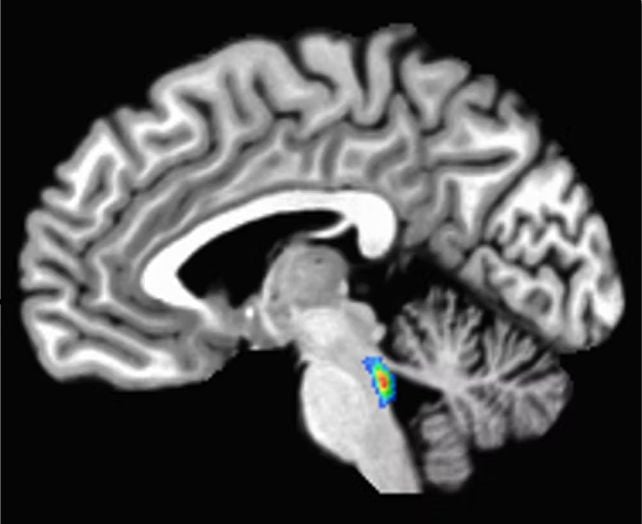

In the earliest of these changes, a tangled version of a protein called tau starts building up in a tiny region deep in the brain involved in sleep, attention, and alertness, called the locus coeruleus. Tau later spreads to the rest of the brain.

The locus coeruleus sits in the brain stem, the lowest part of the brain. Its name, “blue spot,” comes from a pigment called neuromelanin that its cells produce.

Studies suggest that starting in middle age, nerve cells in the locus coeruleus may get damaged by tau buildup, and that damage may correlate with declines in memory. Tau buildup, cell death, and loss of function in the locus coeruleus precedes and predicts Alzheimer’s diagnosis and symptoms.